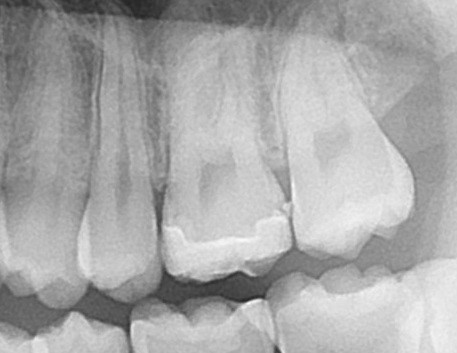

今回のケースに入り、まずはレントゲン写真(エックス線検査)です。

左上の奥歯ですが、よく見ると分かることがあります。